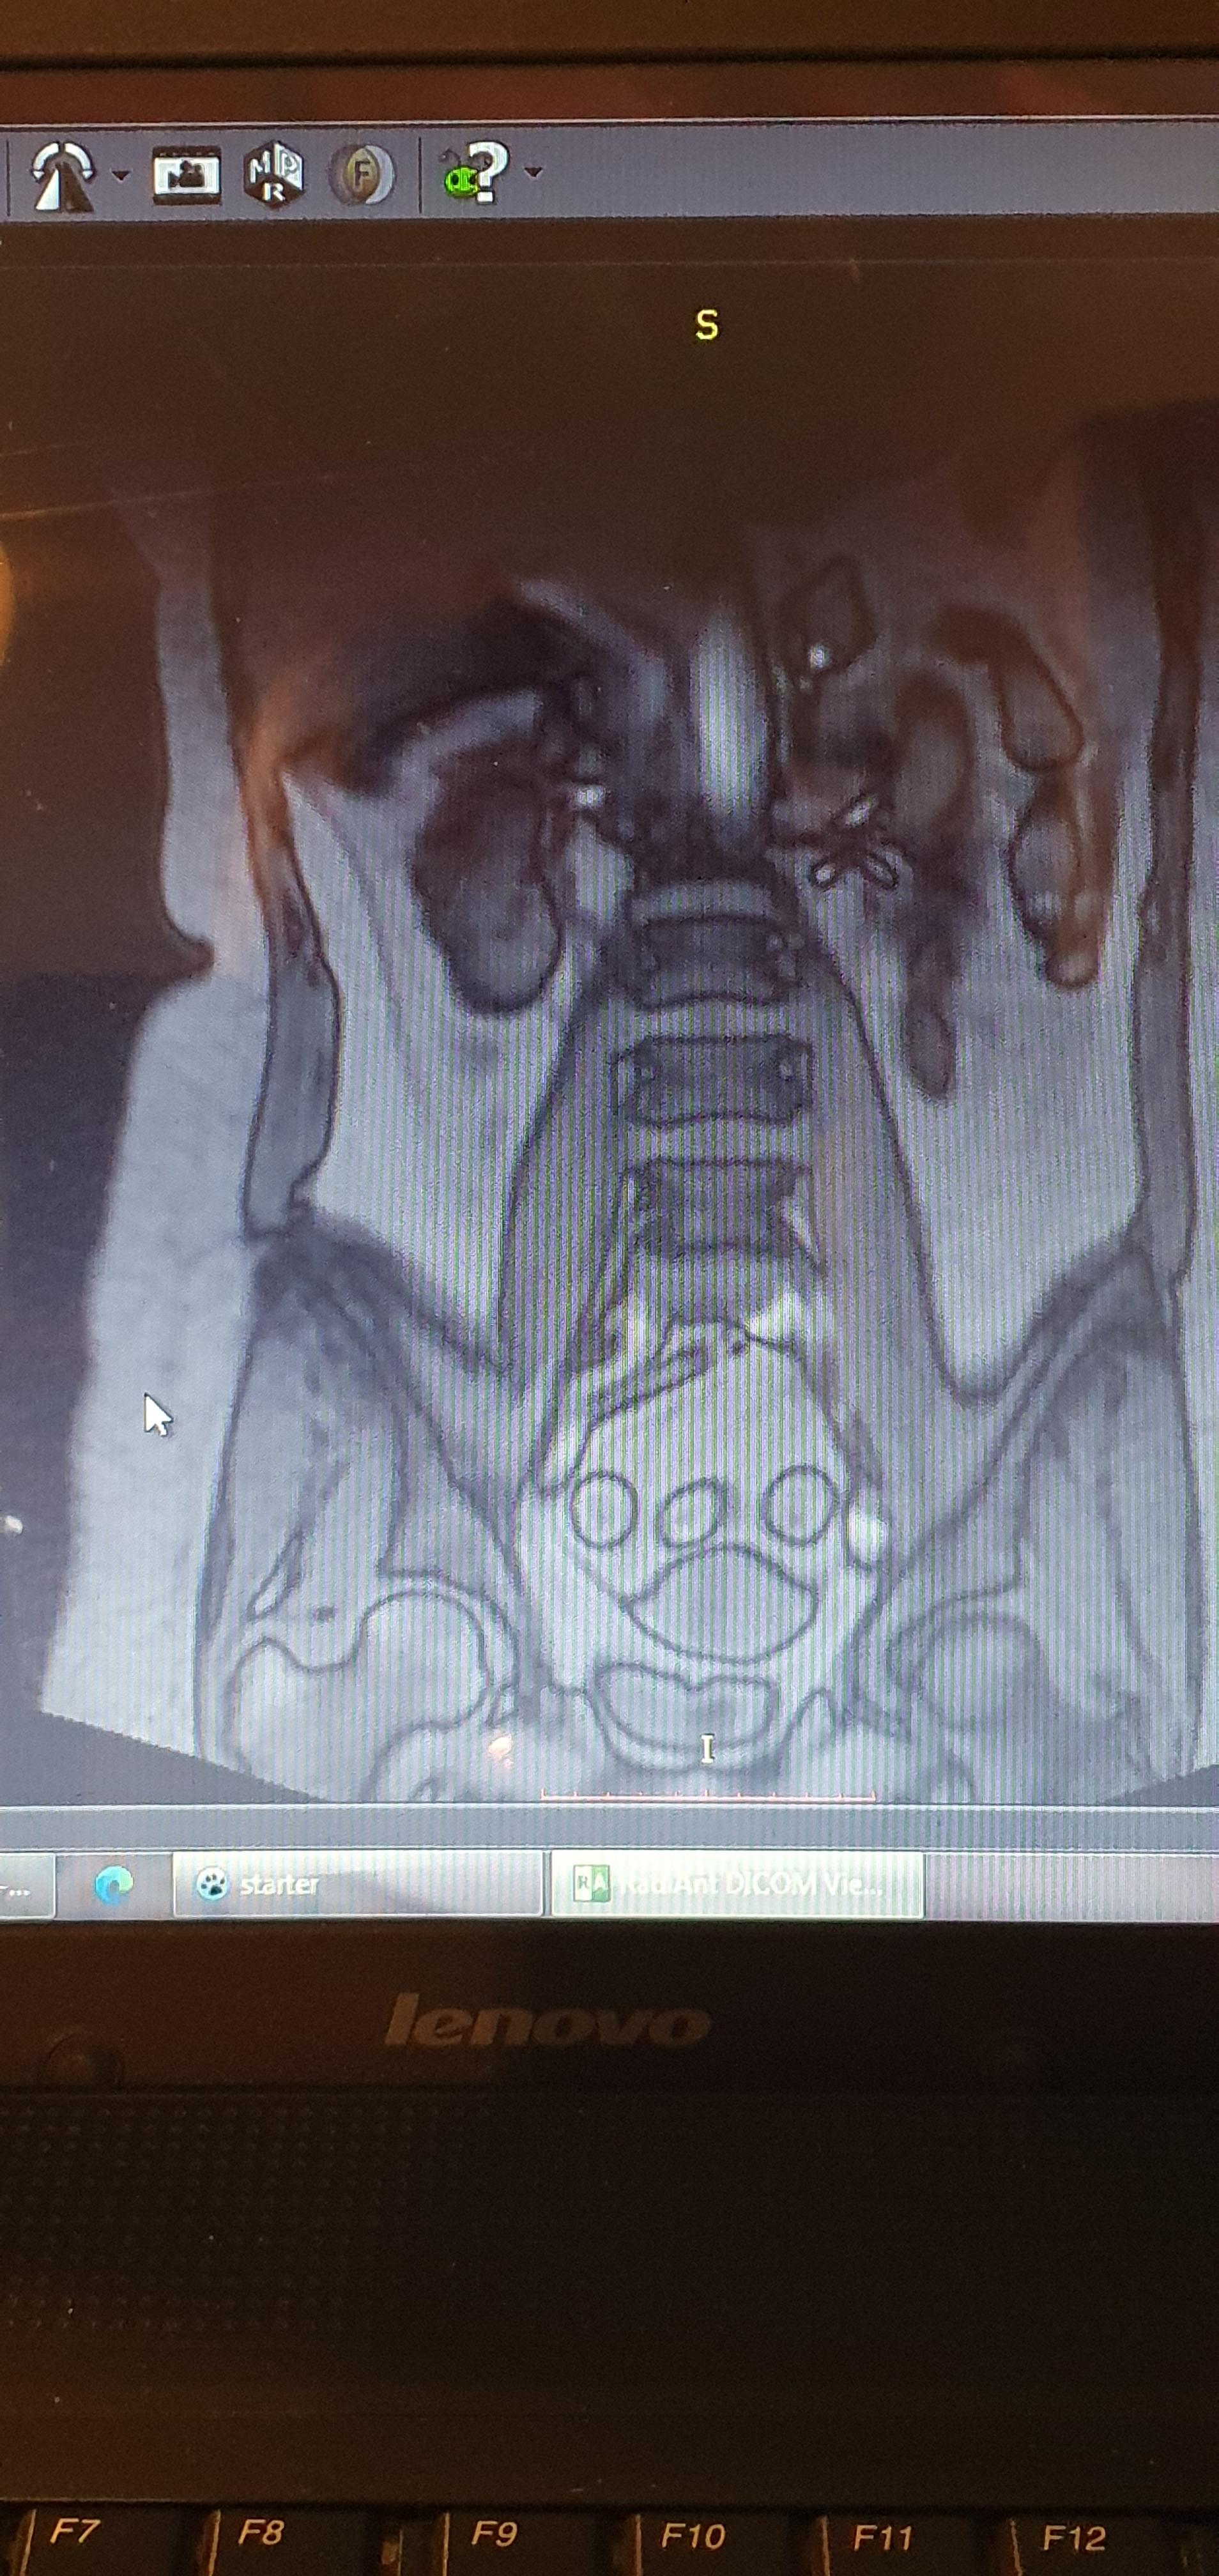

Die Veränderungen müssen immer im Zusammenhang mit der klinischen Symptomatik gesehen werden. Was bedeuten weiße Flecken. Aber es wäre auch möglich dass wenn der weisse Fleck ausserhalb des Knochens ist um die normale Gelenkflüssigkeit handelt. Wenn eine MRT des Abdomens also Bauchraumes auch Abdominal-MRT ansteht handelt es sich in der Regel um sehr gezielte Fragestellungen an Organen. Gestern war ich in einem MRT. Bei der MRT des Beckens handelt es sich um ein bildgebendes Verfahren welches nicht invasiv ist. Es gibt sehr oft unspezifische Veränderungen ohne Krankheitswert.